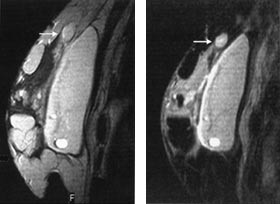

Generelt lader maligne brystkreftsvulster opp intravenøst injiserte MR-kontrastmidler raskere og kraftigere enn godartede svulster og normalt kjertelvev (fig 1). Dette har sammenheng med høyere vaskularitet og økt kapillærpermeabilitet i kreftsvulster sammenliknet med andre typer vev. Tidlige studier rapporterte at brystkreft ble diagnostisert med sensitivitet og spesifisitet på ca. 97 % når en økning i svulstens signalintensitet på 90 % eller mer i løpet av det første minuttet etter kontrastinjeksjon ble brukt som diagnostisk kriterium (11). Med økende erfaringsmateriale er det klart at også mange godartede lesjoner kan lade opp kontrastmiddel raskt og kraftig, særlig gjelder dette enkelte fibroadenomer, fibrocystisk dysplasi og skleroserende adenose (12). Spesifisiteten i senere kliniske MR-studier hvor pasientene har vært utvalgt på bakgrunn av mammografiske og kliniske funn har, avhengig av undersøkelsesteknikk og diagnostiske kriterier, variert fra 37 % til 89 % (13 – 17). Selv om enkelttilfeller av ikke-kontrastoppladende maligne brystvulster er rapportert (18), er den negative prediktive verdien av en MR-undersøkelse som ikke viser kontrastoppladende strukturer i brystet nær 100 %.

Som et resultat av den moderate spesifisitet som oppnås med dynamisk kontrastundersøkelse av brystet, er ulike diagnostiske tilleggskriterier blitt utviklet. Morfologiske egenskaper ved brystlesjonen synes å være vesentlig for å differensiere mellom benigne og maligne svulster. Som ved mammografi er benigne lesjoner ofte velavgrenset med glatte konturer, mens maligne svulster ofte har uskarp avgrensning mot omliggende strukturer og taggete konturer. For at man skal være i stand til å vurdere morfologiske karakteristika optimalt, må bildene ha høyest mulig oppløsning, men da vil bildeopptaket gjerne ta flere minutter, slik at informasjon fra den dynamiske kontrastoppladningen mistes (19). I de fleste studier er det valgt en mellomvei, hvor man ved å bruke en tidsoppløsning på 1 – 2 min og 2 – 3 mm tykke snitt får en akseptabel bildekvalitet for å vurdere morfologiske karakteristika og samtidig et inntrykk av det dynamiske kontrastopptaket i vevet.